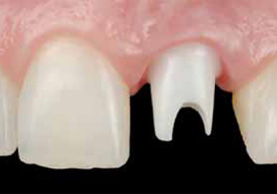

審美的治療は、虫歯や歯周病など機能的に治療することに比べて、機能性に加え見た目の美しさも重視した治療方法です。

欠けてしまった歯並びや歯の色などを修復する際に、回りの歯の色と合わせて審美性(見た目)を回復させたり、黄ばんでしまった歯や歯ぐきを従来のような健康的な色に回復させるなどの治療を行うことで、自然に近い美しい口元にすることが可能です。

「歯を白くキレイにしたい」 「歯並びを整えたい」とお考えの方に、ご要望をお聞きしながら治療計画を作成し、顔立ち・骨格などを詳細に検査したうえで、口元に調和した1クラス上の治療を提供します。

当院では、白く透明感があり、天然歯のようで目立たないながら、金属やセラミック以上の強度のある「ジルコニア」や、比較的低コストながら、長く使えるセラミックと歯科用プラスチックを合わせた「ハイブリッド」なども提供しております。